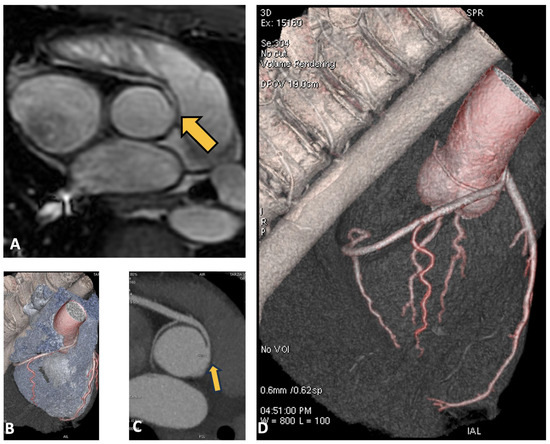

3.4. Case 4: Coronary Fistula

| 4 | 27 | Volleyball | Coronary fistula | Syncope | No |